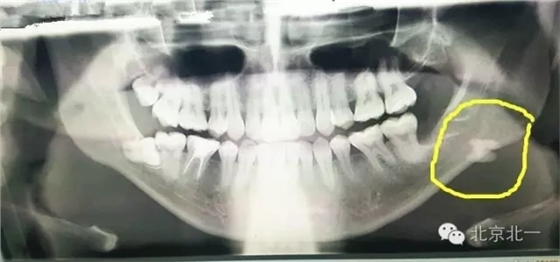

圖一:全景片可見下頜骨下緣高密度影像,清晰可見。